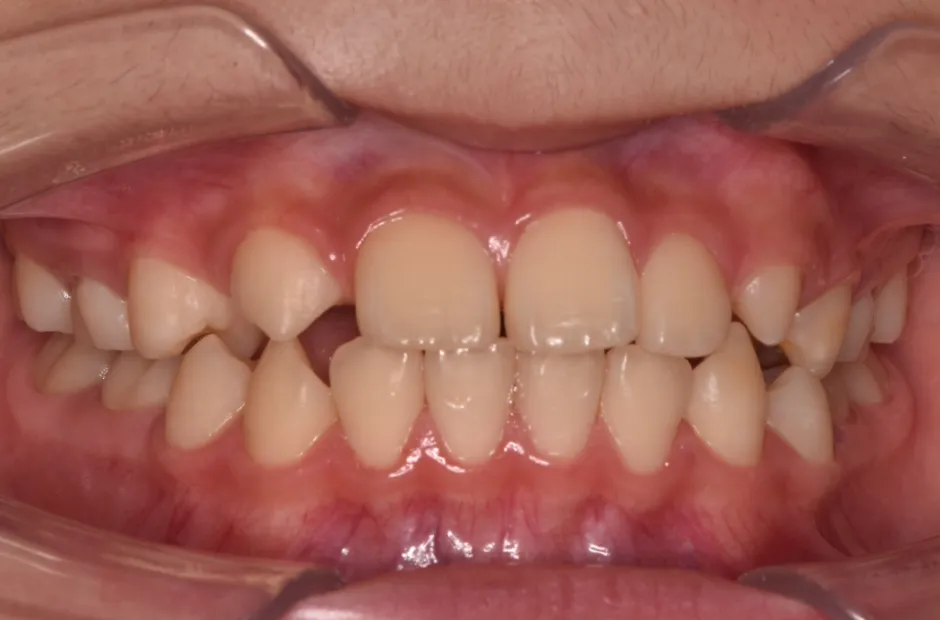

出っ歯

| 診断名・主訴 | 出っ歯 |

|---|---|

| 年齢・性別 | 16歳・男性 |

| 治療期間・回数 | 1年4か月 |

| 治療に用いた主な装置 | ブラケット |

| 抜歯部位 | 上顎4,4 |

| 治療費 | 60万円(税抜) |

| リスク・副作用 | 装置による違和感・疼痛・歯肉退縮・歯根吸収・虫歯のリスクなど |

治療前

治療後